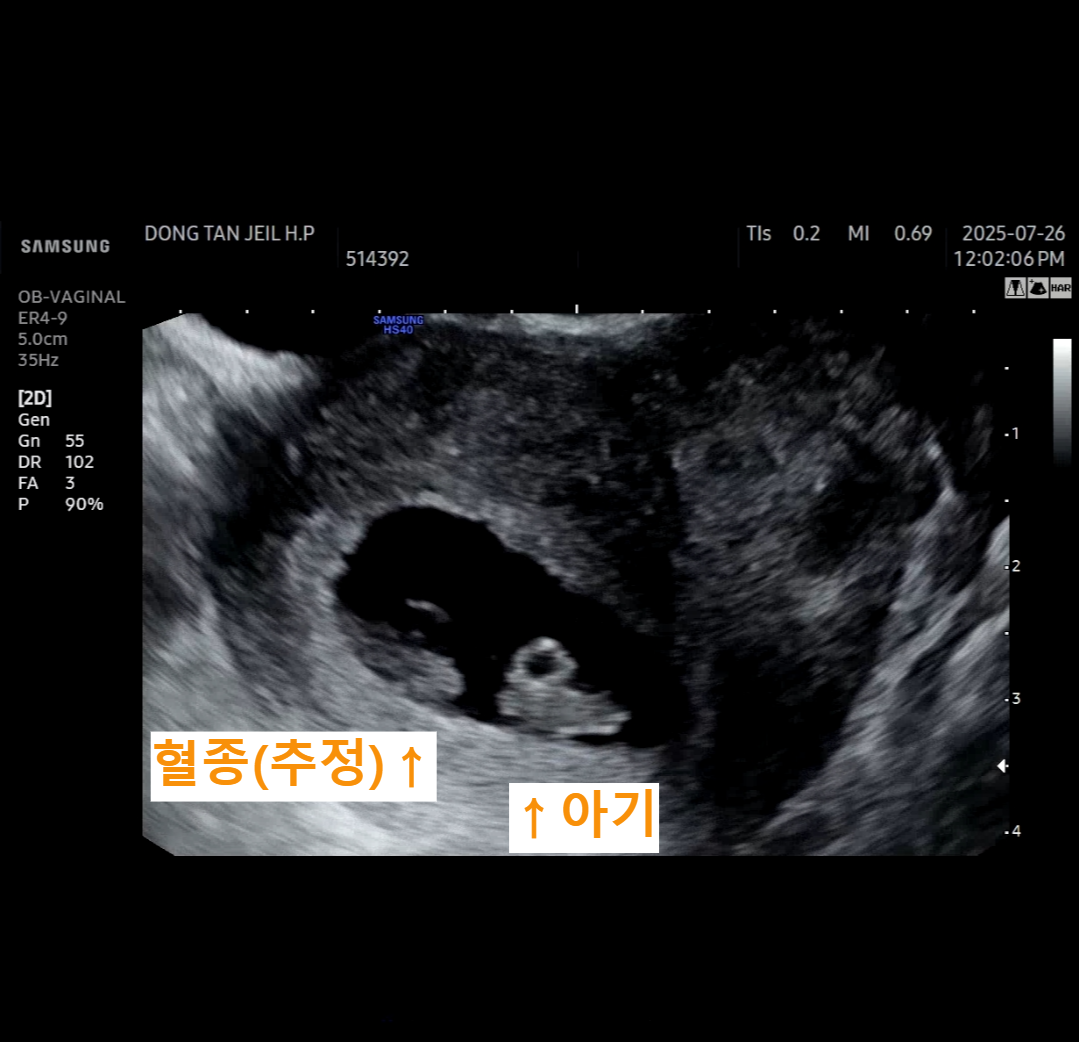

저 역시 임신 7주 2일차 초음파를 보러 갔다가 이런 얘기를 들었습니다.

아기 심장은 잘 뛰고 있고 크기도 약 1.1cm로 정상이지만,

태아 옆에 작은 혈종이 의심된다는 설명을 들으니 순간 걱정이 밀려왔죠.

초음파 사진을 보면 아기(태아) 옆에 까맣게 보이는 음영이 있습니다.

이것이 바로 **"혈종(subchorionic hematoma, 피하혈종)"**으로 의심되는 구조인데요.

의학적으로는 태반과 자궁벽 사이에 출혈이 생기며, 그 피가 고여 있는 상태를 말합니다.

저의 경우도 태아의 심장박동이 잘 뛰고 있었고, 혈종은 작게 관찰되었기 때문에 의사 선생님께서도 "크게 걱정할 필요 없다"고 설명해주셨어요.